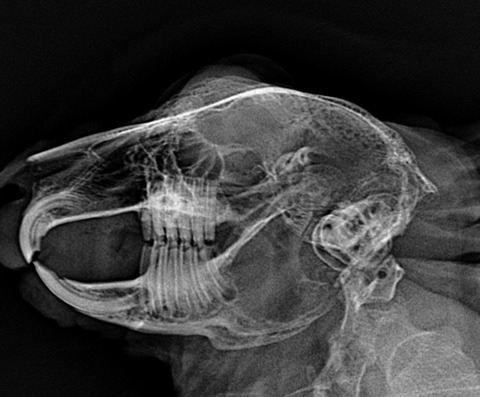

このように不正咬合がある子は歯根も正常ではないことがほとんどのため、歯根膿瘍や鼻涙管閉塞も起こりやすいですが、それはまた別の記事で

綺麗な歯根